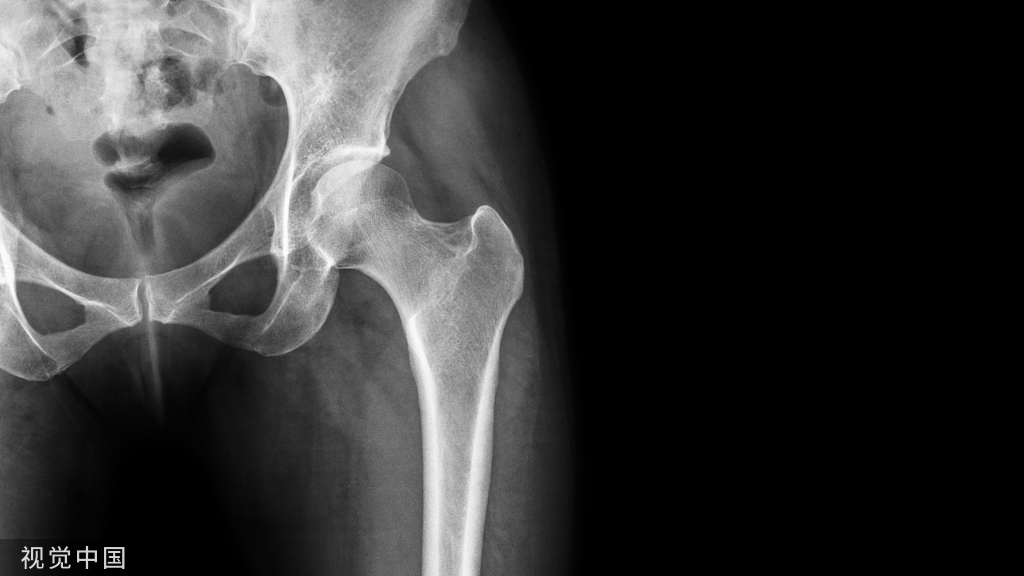

治病讲究对症下药,按阶段治疗。因此判断玻璃酸钠对膝关节炎是否有效之前,我们可以先确定膝关节的退变阶段,具体参照下图。

玻璃酸钠仅对轻中度的关节炎有效,也就是说您膝盖的X线片如果类似于前三个图的话可以试试,如果已经到3级4级的话建议不要做无谓的尝试(4)。